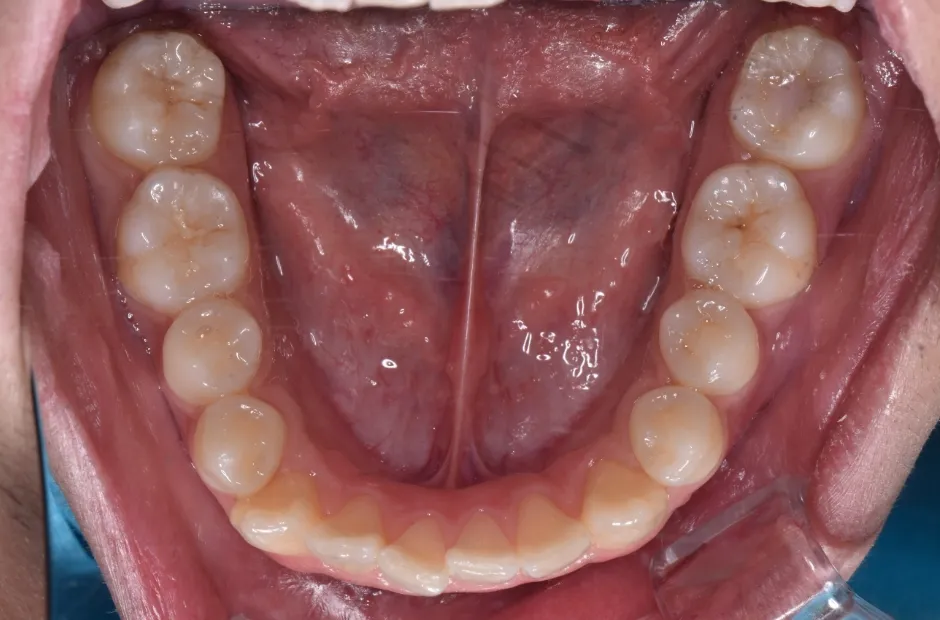

叢生

| 診断名・主訴 | 叢生 |

|---|---|

| 年齢・性別 | 43歳・女性 |

| 治療期間・回数 | 2年7か月 27回 |

| 治療に用いた主な装置 | 舌側矯正 |

| 抜歯部位 | 両顎4,4 |

| 治療費 | 100万円(税抜) |

| リスク・副作用 | 装置による違和感・疼痛・歯肉退縮・歯根吸収・虫歯のリスクなど |

治療後